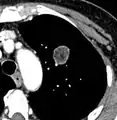

Low attenuating nodule (in this case a fat containing hamartoma).[9]